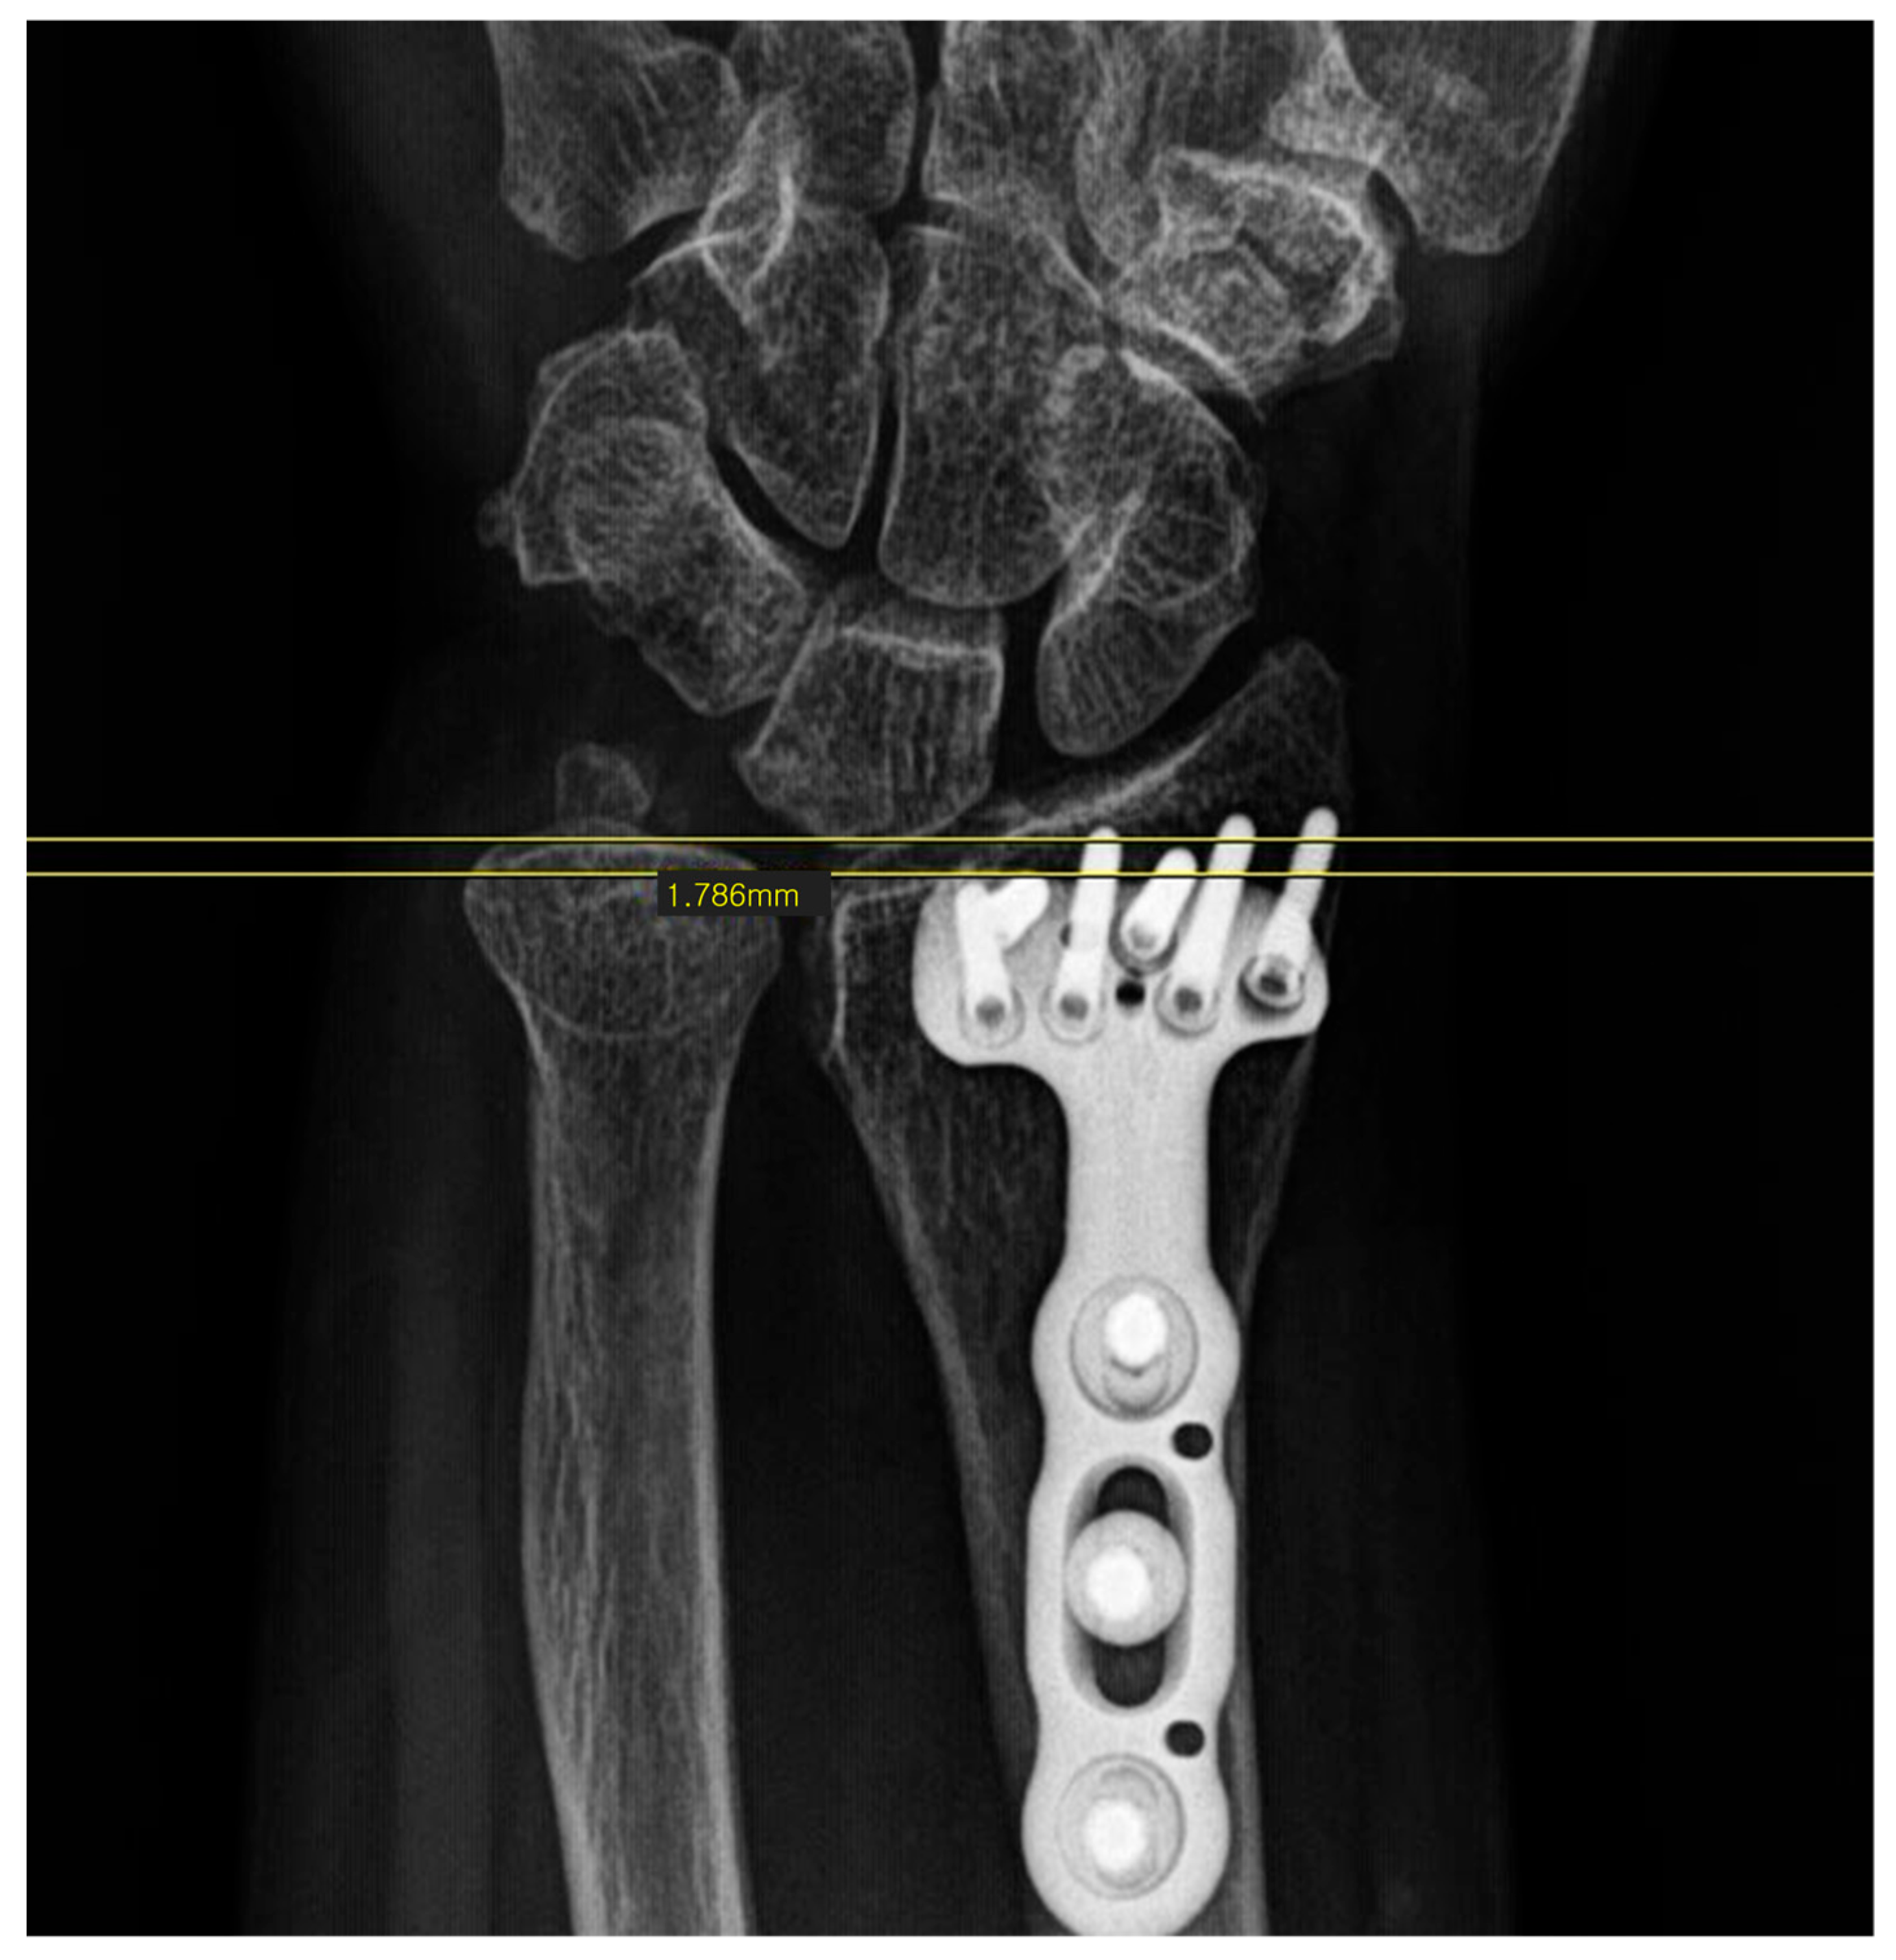

Radiologic Evaluation: Radiologic parameters, specifically ulnar variance and ulnolunate distance, were measured immediately postoperatively and at the final follow-up. Measurements were performed twice by two orthopaedic residents independently, and the mean values were used for analysis. Ulnar variance was measured on standard PA wrist radiographs (taken with the shoulder abducted 90°, elbow flexed 90°, and forearm in neutral rotation) using the method of perpendiculars. To compensate for potential measurement errors in ulnar variance, we also measured the ulnolunate distance, defined as the shortest distance between the lunate ulnar corner and the most convex point of the ulnar head (Figure 1 and Figure 2). Additionally, the location of the lunate cyst was evaluated using preoperative computed tomography (CT). Preoperative CT was obtained as part of routine clinical care when intra-articular involvement or complex fracture morphology required further assessment for surgical planning, and it was not performed solely for research purposes. CT acquisition followed our institutional clinical protocol, and no additional imaging was requested specifically for this retrospective study. Cysts were classified as dorsal or palmar based on sagittal CT images. Cysts that could not be clearly localized to either side were categorized as “unclassified” (Figure 3).

Figure 1. Measurement of ulnar variance.

Surgeries 07 00039 g001